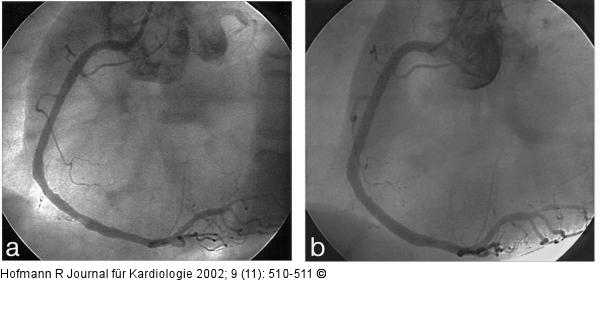

Abbildung 4a: Mobiler Thrombus der RCA bei NSTEMI Kontrollangiogramm nach medikamentöser Therapie: weitgehend unveränderter Füllungsdefekt. |

Abbildung 4a: Mobiler Thrombus der RCA bei NSTEMI

Kontrollangiogramm nach medikamentöser Therapie: weitgehend unveränderter Füllungsdefekt. |